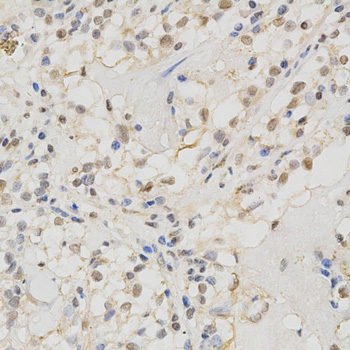

| Tested applications | WB IHC IF |

| Recommended Dilution | WB 1:500 - 1:2000 IHC 1:50 - 1:200 IF 1:50 - 1:200 |

ilution of 1:100 (x400 lens).